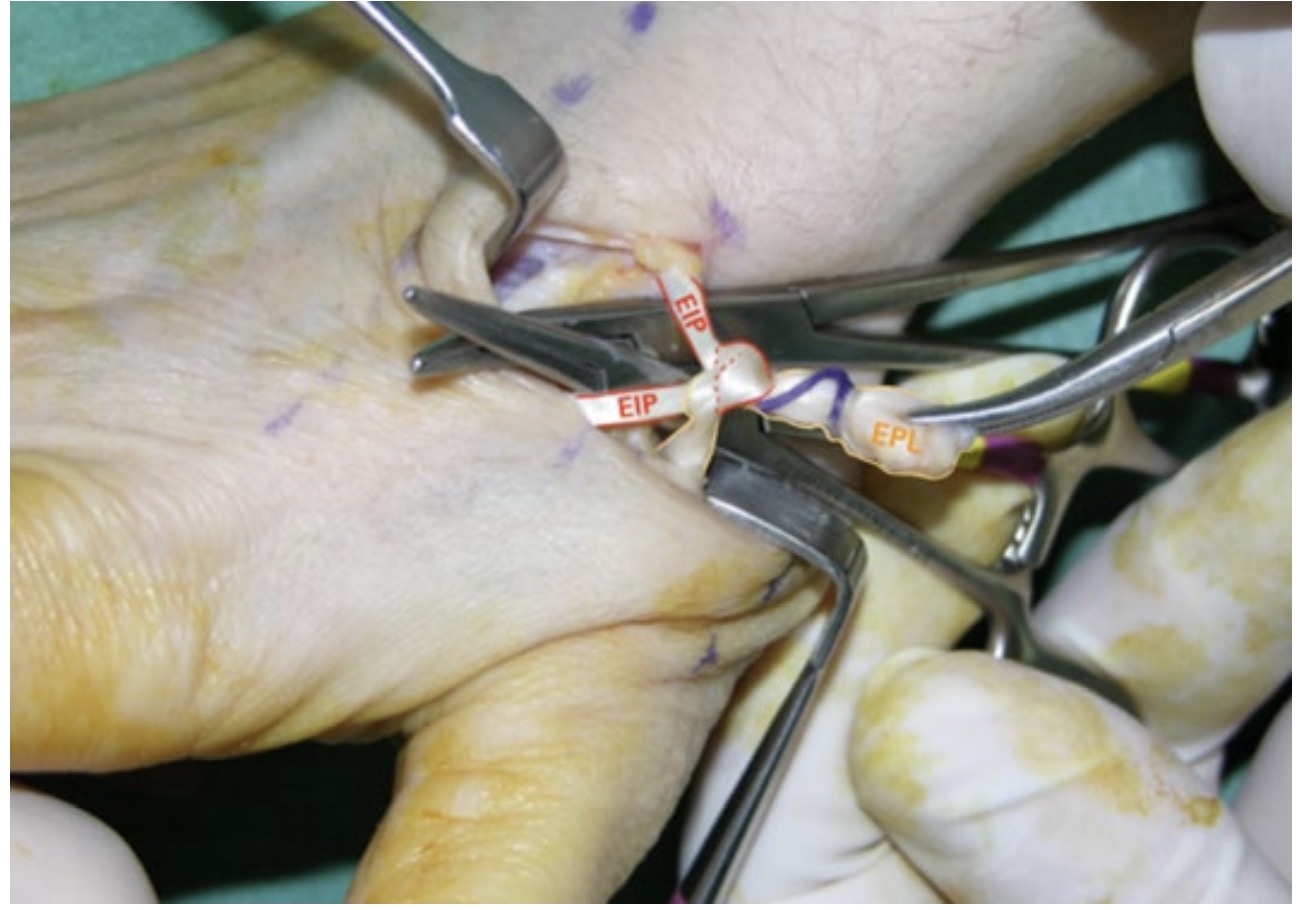

La técnica del lazo para la reparación de lesiones tendinosas, especialmente en la reparación de la rotura del extensor largo del pulgar, ha demostrado eficacia y resultados clínicos satisfactorios. Para esta, se ha desarrollado la técnica del lazo en las transferencias del extensor corto del pulgar o del extensor propio del índice al extensor largo del pulgar deteriorado. La transferencia realizada para reparar el extensor largo del pulgar con la técnica del lazo ha sido eficaz y segura, y se ha conseguido la recuperación de la extensión del pulgar, con lo que se ha reafirmado el valor del nudo con lazo como medio de unión.

Diseño e implementación del nudo con el lazo, para la reparación del extensor largo del pulgar, utilizando, como transferencia dinámica, el extensor corto del pulgar o el extensor propio del índice (figs. 13-20).

El método presentado diseña de un modo novedoso la forma de unir dos elementos de aspecto cordonal que garantiza su fortaleza y su seguridad. Es importante reseñar que el desarrollo del método se llevó a cabo en un entorno quirúrgico que buscó reparar el tendón extensor largo del pulgar con una transferencia dinámica en la que se utilizó la técnica del nudo con lazo continuo transfixiante para unir otro tendón motor al extensor largo del pulgar lesionado. Es un nudo para enlazar dos elementos.

Se denomina “lazo” por la forma que presenta antes de envolver el extensor largo del pulgar, “continuo” por no soltar la inserción del tendón motor y “transfixiante” por pasar por el interior con un ojal en el seno del extensor largo del pulgar antes de realizar la lazada. Aportar algo nuevo tanto a la industria en general como a la técnica quirúrgica antes reseñada fundamentó el objetivo de este trabajo para conseguir su difusión científica. Más aún cuando se ha comprobado clínicamente la fiabilidad, seguridad y fortaleza de la unión conseguida, avalada por los resultados obtenidos en otros trabajos. Antes de esta técnica, otros métodos han sido publicados en la literatura para realizar esta reparación y también han mostrado resultados satisfactorios. La técnica de unión descrita por Pulvertaf es quizás la más utilizada y comentada. Así mismo, múltiples estudios de carácter biomecánico analizan de forma comparativa las diversas formas de enlace y unión de estructuras en el ámbito de la cirugía de reparación tendinosa, Pulvertaft weave, spiral linking, side to side, end weave y tipo lazo, analizando fuerza, resistencia y elasticidad. El fin de este trabajo no fue competir con ellas, sino aportar una herramienta más, para enfrentarse a la reparación del extensor largo del pulgar, con sus valores antes reseñados y, al mismo tiempo, la exportación al conocimiento industrial, para su empleo en nuevas aplicaciones.